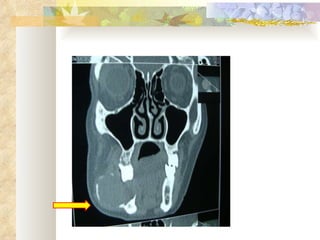

INVESTIGATIONS Radiological – OPG, lateral occlusal mandibular radiograph Complete blood picture, CT, BT Incisional biopsy

Bicortical expansion

RADIOLOGICAL FEATURES Unilocular radiolucency, especially early lesions that often progress to multilocular ( soap-bubble, honeycomb ) May be associated with impacted tooth Cortical expansion and thinning Resorption of adjacent tooth roots, displacement of teeth can be seen